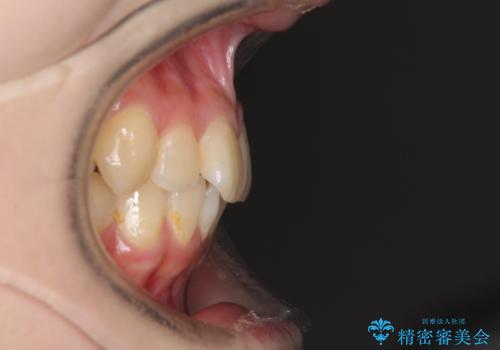

- 上下歯列全体のデコボコを気にして来院された患者様です。

主に下顎歯列全体の後方移動とIPR(歯と歯の間を削る)によってデコボコが解消するように設計し、インビザラインにより治療を行うこととしました。

奥歯の知覚過敏が顕著となり、その影響で奥歯の咬み合わせ改善のための顎間ゴムの装着ができず、咬合を仕上げるまでに長い期間を要することとなりました。